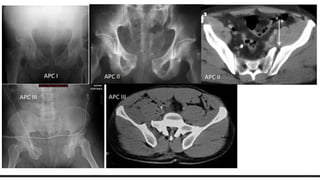

● Young- Burgess classification

○ Anterior posterior compression ( APC)

■ APCI. symphyseal widening> 2.5cm

■ APCII. Symphyseal widening > 2.5cm, anterior SI diastasis

● Disruption of the sacrospinous and sacrotuberous ligaments

■ APC III. disruption of anterior and posterior SI ligaments

● Young- Burgessclassification ○ Anterior posterior compression ( APC) ■ APCI. symphyseal widening> 2.5cm ■ APCII. Symphyseal widening > 2.5cm, anterior SI diastasis ● Disruption of the sacrospinous and sacrotuberous ligaments ■ APC III. disruption of anterior and posterior SI ligaments